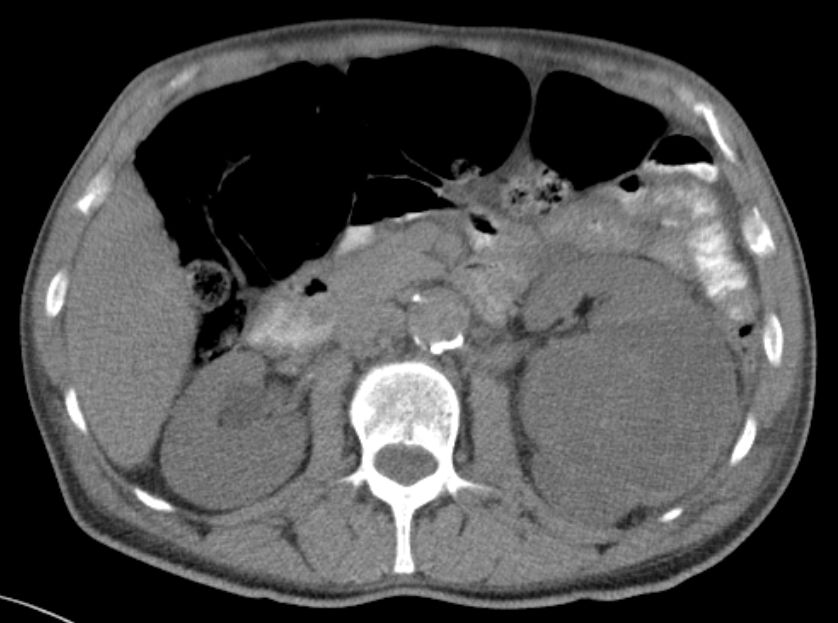

61-jähriger Mann bei dem notfallmäßig eine Tumornephrektomie links wegen Sepsis und nekrotisch zerfallendem, infiziert rupturiertem NZK links cT3b pM0 M0 G2 durchgeführt wurde. Makroskopie: 15 x 9 x 10 cm großes Nephrektomiepräparat. Im Zentrum überwiegend im Hilusbereich entwickelt, ein stark nekrotisch zerfallender, 8 cm großer Tumor.

Mikroskopie: Der Tumor zeigt papilläre, teilweise tubuläre Strukturen.

Die Einzelzellen enthalten vergrößerte hyperchromatische Zellkerne mit prominenten Nukleolen.

Das Zytoplasma ist teilweise klar, teilweise schwach eosinrot angefärbt.

Teilweise erkennt man Tumoranteile mit girlandenförmigen Proliferaten.

Immunhistochemie: z.T positiv mit CD 10. Herdförmig kräftig positive Reaktion mit Zytokeratin 7 und Vimentin. CD 117, Melan A und HMB 45 negativ.

5 Monate später Rezidiv. Th.:Pazopanib